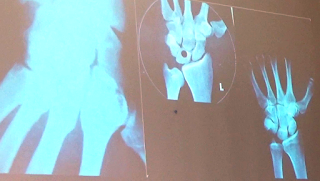

En la imagen de abajo tratamos de saber qué

mano es o que rodilla es para lo cual necesitamos el apoyo de la

orientación radiográfica.

La orientación anatómica está basada en reparos:

Artificiales: son letras números plomados que van aparecer siempre a

la derecha de la imagen radiográfica. Se usa para orientarnos en las

cierta cantidad de radiación se ven representadas en la película radiográfica. Esta condición de las estructuras anatómicas

la podemos observar en la imagen de abajo donde se observa a la izquierda una

figura en la que se muestra una imagen radiográfica de la mano y muñeca. Es

evidente en esta imagen la presencia de imágenes radiopacas que san información

sobre los huesos de esta región. A la derecha por el contrario fue necesario la

utilización de un medio de contraste, que leve su espesor, para poder observar

la red arterial de la mano.